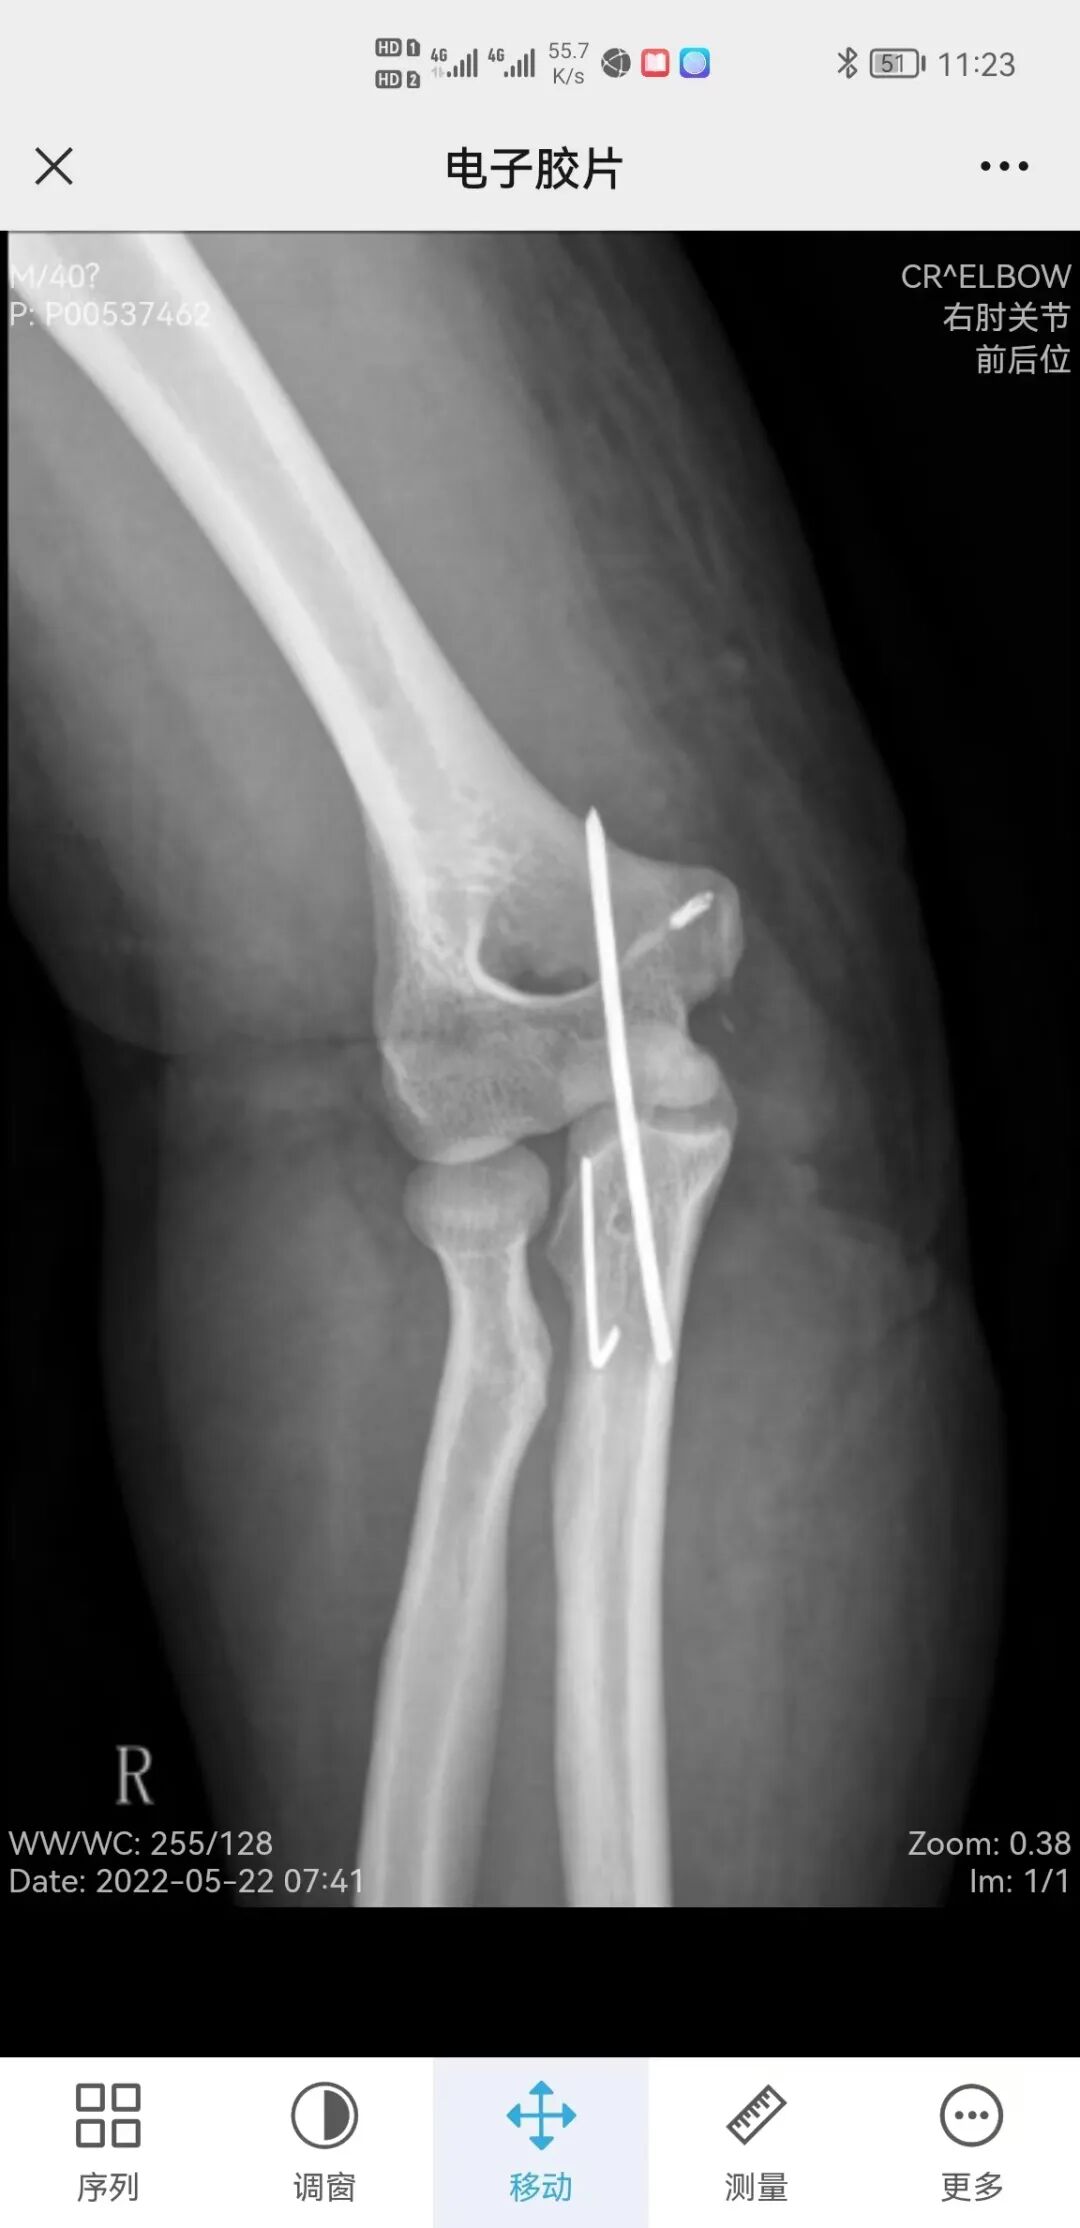

患者慕名来到了龙口市中医医院针灸康复科,姜恒坤主任接诊了他,经过问诊得知原来患者1月前不慎跌倒,右手触地后导致肘关节骨折,做完手术后一直未进行康复治疗,此次来诊时已去除内固定钢针1枚,尚有一枚钢针断端残留骨折处。

姜恒坤主任仔细地查看了片子并进行了细致的体格检查:右肘关节有两处长约8cm-10cm的手术切口瘢痕,局部肿胀,鹰嘴后有压痛。肘关节屈伸范围在90-110°之间,活动明显受限。姜恒坤主任立即召集治疗师团队进行了初次康复评定,指出:主要问题为“右肘关节活动受限”。

患者较年轻,术后骨折处愈合较好,自身康复欲望强烈,期望值高,对于高强度康复训练耐受性强,且积极主动。评估判定短期康复目标为:止痛消肿、改善关节活动度。长期康复目标为:关节活动度正常,回归社会。不足之处,骨折处有内固定断端残留,需注意定期拍片检查,防止游离,造成二次损伤。辩证论治予以口服中药汤剂,局部应用中药封包热敷后,立即给予关节松动技术治疗,治疗后予以作业疗法巩固治疗效果,仅1周时间,患者右肘关节的主动屈伸角度即达到了正常,不再影响日常生活。